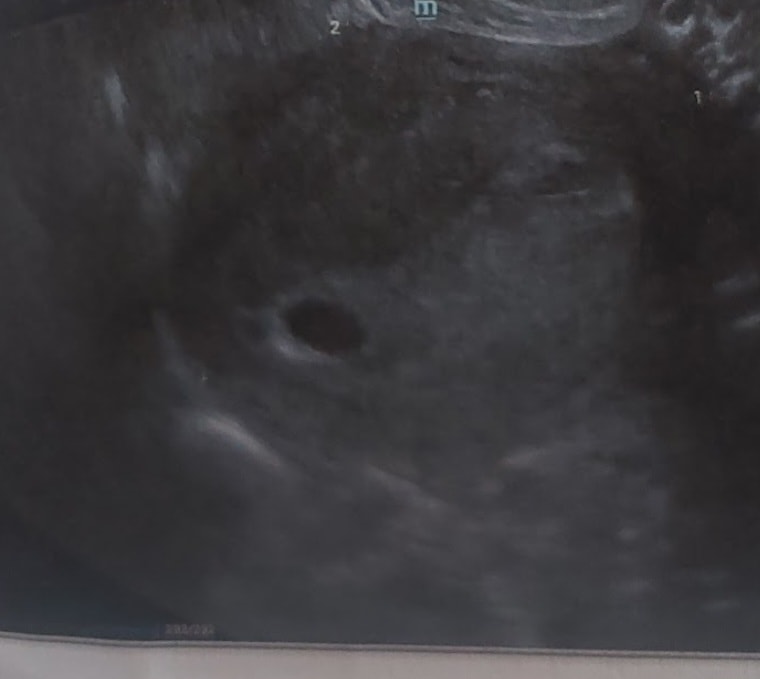

Светлана ,

Вот тоже моё УЗИ 5,5 недель, тоже сказали что эмбриона ещё не видно . А у девушки прям явно точечку вижу😍

Лизик , вот ещё другое фото УЗИ, тут видно ЖМ, тогда по размерам был 16 мм, возможно у вас тоже ЖМ, но утверждать не буду)) я искренне вас поздравляю 😊🙏🏻💕